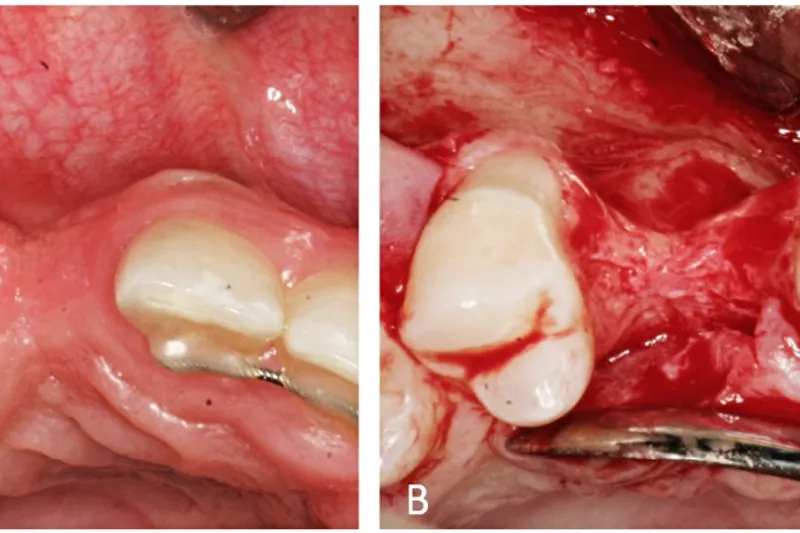

I et tandløst område, hvor det er tiltænkt at erstatte en eller flere manglende tænder med en protetisk restaurering, vil valg af behandlingsstrategien ofte være afhængigt af flere faktorer, herunder højden og bredden af processus alveolaris. Dette gælder ved erstatning med en konventionel bro, en aftagelig protese og i særdeleshed, hvis en implantatunderstøttet protetisk restaurering vælges. Ved manglende tandanlæg, mistede tænder som følge af traume eller kirurgisk fjernelse vil dimensionerne af processus alveolaris ofte være reducerede, således at der kan være behov for knoglegenopbygning enten før eller i forbindelse med implantatindsættelsen. Omhyggelig behandlingsplanlægning omfattende en klinisk og radiologisk undersøgelse af processus alveolaris er derfor vigtigt for at afdække behovet for knoglegenopbygning og gennemføre behandlingen med et forudsigeligt behandlingsresultat. Nærværende oversigtsartikel gennemgår forskellige metoder til klinisk og radiologisk vurdering af dimensionerne i det tandløse område med særlig fokus på efterfølgende implantatindsættelse inklusive anbefalinger for anvendelse af cone beam computer-tomografi.

In an edentulous area planned for replacement of one or more teeth with a prosthetic restoration, the choice of treatment strategy is frequently influenced by several factors, including height and width of the alveolar ridge. This applies to replacement with a conventional bridge, a removable prosthesis, and especially in relation to implant-supported prosthetic restorations. In case of developmental absence of teeth, tooth loss due to trauma or surgical removal, the dimensions of the alveolar ridge may often be reduced, which may create a need for bone augmentation either before or in conjunction with implant placement. Thus, careful treatment planning including a clinical and radiological examination of the alveolar ridge is important to assess the need for bone augmentation and to conduct the treatment with a predictable treatment outcome. The present review presents various methods for clinical and radiological assessment of the dimensions of the edentulous area with special focus on subsequent implant placement including guidelines for use of cone beam computed tomography.